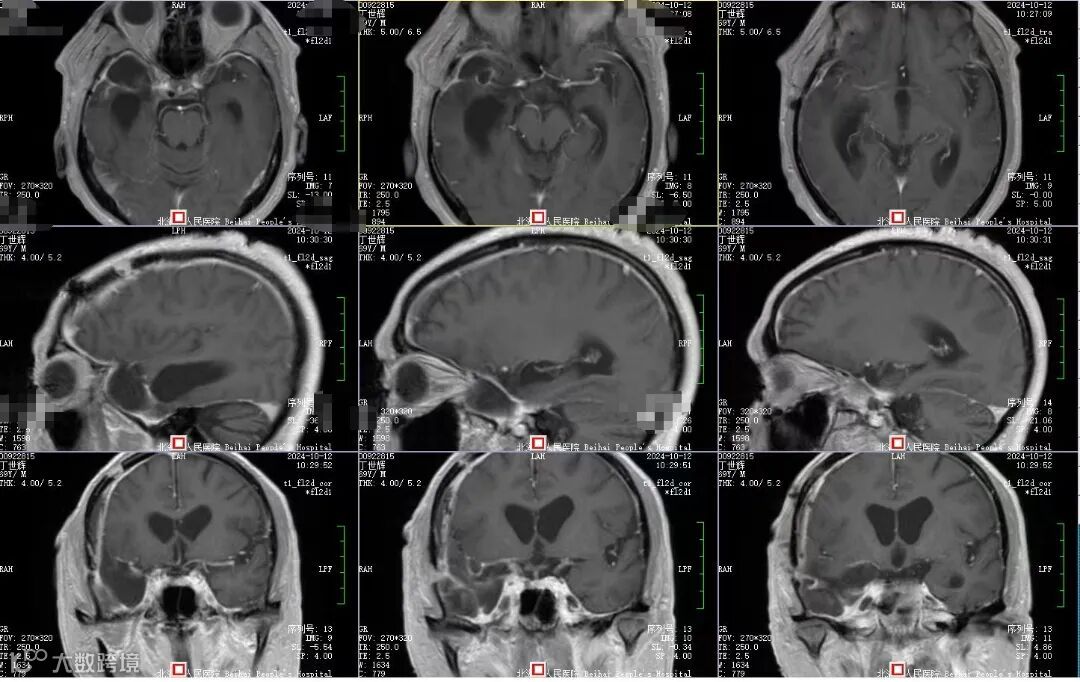

10月下旬,刘叔回到医院复查磁共振,提示肿瘤没有残留或复发,便给主刀医生邓峰送来锦旗表示感谢。